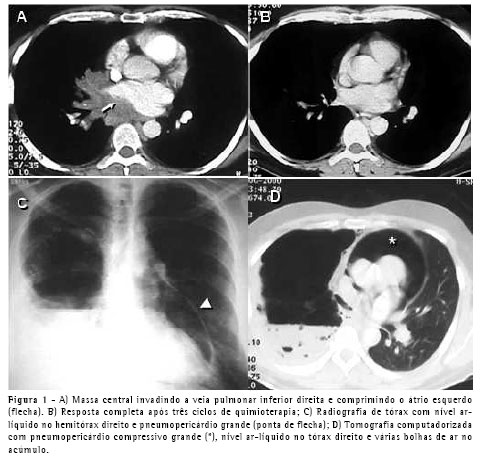

Um paciente do sexo masculino, com 40 anos, apresentando fibrilação atrial consultou um cardiologista. Ele não era tabagista e suas radiografias de tórax mostraram adenopatia hilar no lobo inferior direito. A tomografia computadorizada (TC) revelou uma massa central invadindo a veia pulmonar inferior e comprimindo o átrio esquerdo (Figura 1A). Uma lesão endobrônquica foi vista no brônquio lobar inferior direito e fez-se uma biopsia. Os resultados foram compatíveis com carcinoma neuroendócrino de grandes células. O paciente foi submetido a três ciclos de quimioterapia à base de cisplatina e a radioterapia. As TCs subseqüentes (Figura 1B) e exames broncoscópicos revelaram uma resposta altamente positiva ao tratamento Ele foi submetido a uma pneumonectomia direita radical incluindo uma porção do contorno do átrio esquerdo (primeira margem de ressecção positiva na altura da veia pulmonar inferior) e do pericárdio para-hilar. O defeito pericárdico foi enxertado com pericárdio bovino e um orifício de 2 cm foi deixado na linha de sutura para permitir que fluidos ou ar pudessem sair livremente do saco pericárdico. O paciente recebeu alta no quinto dia de um pós-operatório curto e sem intercorrências. Dez dias depois, ele retornou ao hospital apresentando hipotensão postural e dor subesternal constante. A radiografia de tórax mostrou pneumopericárdio (Figure 1C), confirmado na TC, que também revelou múltiplas bolsas de ar e nível ar-líquido no espaço pleural, sugerindo fístula bronco-pleural (Figura 1D). Ele foi internado no hospital, um tubo torácico (36Fr) foi inserido no espaço pleural direito, e a broncoscopia mostrou uma pequenina (1.0 mm) fístula no coto brônquico. Não havia sinais ou sintomas de infecção e o líquido pleural estava claro, com menos do que 300 células, das quais 80% eram eosinófilos. O paciente não apresentou fuga aérea intra-operatória ou pós-operatória através do tubo torácico. Os antibióticos foram dados, e a evolução foi excelente. O tubo torácico foi retirado no décimo dia pós-operatório. O pneumopericárdio sintomático desapareceu imediatamente após uma drenagem pleural e não houve nenhum empiema ou outras complicações.